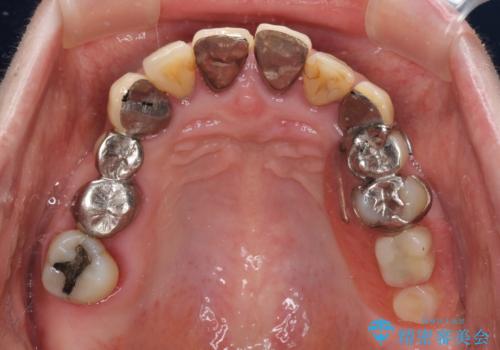

まずは抜歯が必要な歯を抜歯した上で仮歯に置き換え、インプラント埋入や歯周外科処置、根管治療を行うこととしました。